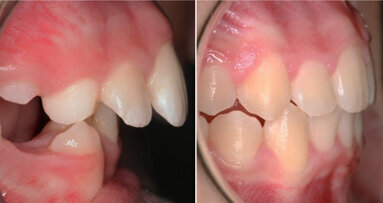

Fig. 2: Clinical image of patient. Note the wear of the metal abutments due to disengagement of the nylon retention inserts as a result of fulcrum during function.

The patient continued to experience problems with the lower denture coming loose during function and required frequent replacement of the nylon male inserts; replacement with Extended Range inserts did not vary performance. The metal abutments demonstrated considerable wear as well (Fig. 2). Relining the lower denture did not improve the performance of the anchor system.